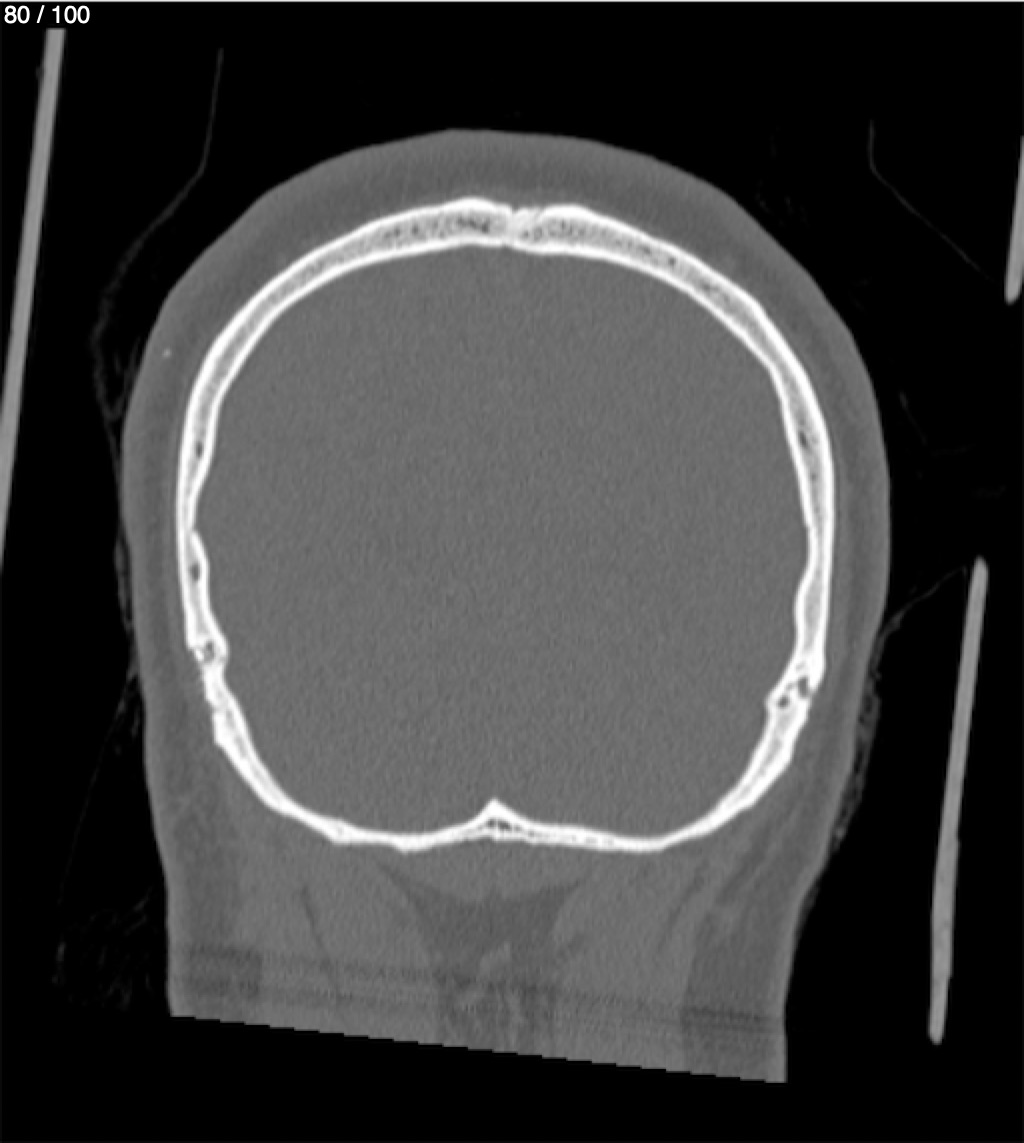

Reybet Garcia Fuentes 30A - T.C Craneo